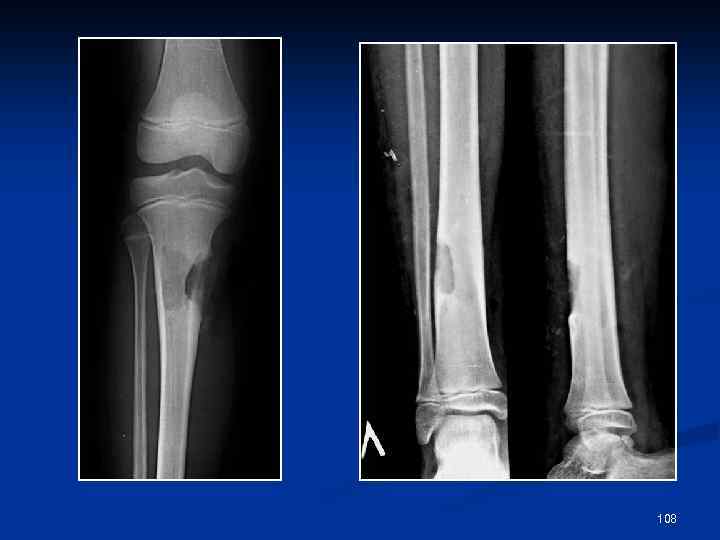

ОСТРЫЙ ГЕМАТОГЕННЫЙ ОСТЕОМИЕЛИТ ü ü ü ü Рентгенологические симптомы появляются к концу 2 -й недели после острого начала болезни (у детей- к концу 1 -й недели) Поражение метафиза, распространение на диафиз кости Локальный остеопороз Очаги деструкции костной ткани (сначала с расплывчатыми неровными контурами) Периостальные наслоения (линейные, слоистые, бахромчатые) Секвестры (корковые) Образование свищей 107

108